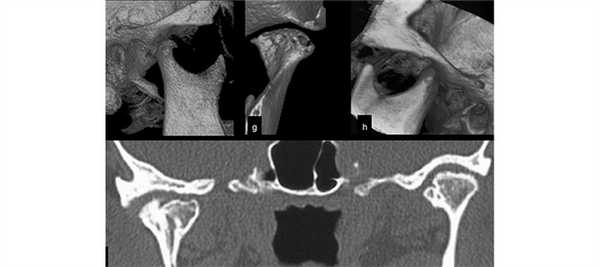

(Слева) На панорамной рентгенограмме у пациента с двухлоронним передним вывихом визуализируется правый мыщелок, смещенный кпереди и кверху относительно сулавного возвышения. Обратите внимание на явный передний открытый прикус, в то время как моляры находятся в окклюзии.

(Справа) На панорамной рентгенограмме у этого же пациента определяются аналогичные изменения слева. Открытый прикус обусловлен неправильным передним положением мыщелка, контакт задних зубов - его верхним положением.

2. Рентгенография при вывихе височно-нижнечелюстного сустава (ВНЧС):

• Радиографические признаки:

о Передне-верхнее положение мыщелков по отношению к суставному возвышению

3. КТ при вывихе височно-нижнечелюстного сустава (ВНЧС):

• КТ в костном окне и КЛКТ:

о Хронический вывих: атрофия суставного возвышения и уплощение суставной ямки

(Слева) На рентгенограмме в боковой проекции у этого же пациента определяется прогнатическое положение нижней челюсти и открытый передний прикус вследлвие передне-верхнего смещения мыщелков нижней челюсти.

(Справа) На сагиттальной КЛКТ правого и левого мыщелков у этого же пациента определяется, что мыщелки расположены спереди и сверху относительно сулавных возвышений. Обратите внимание, что мыщелки имеют нормальную форму, а кортикальная плалинка не изменена.